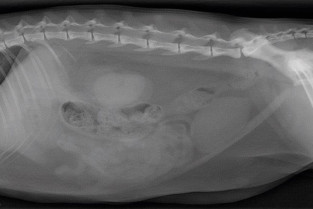

- décrire les principes à respecter pour obtenir une radiographie abdominale de bonne qualité ;

- adopter une méthodologie pour interpréter les affections de la cavité péritonéale et rétropéritonéale chez les carnivores domestiques ;

- décrire l’aspect normal et anormal des organes péritonéaux et rétropéritonéaux chez les carnivores domestiques ;

- détecter une obstruction digestive.